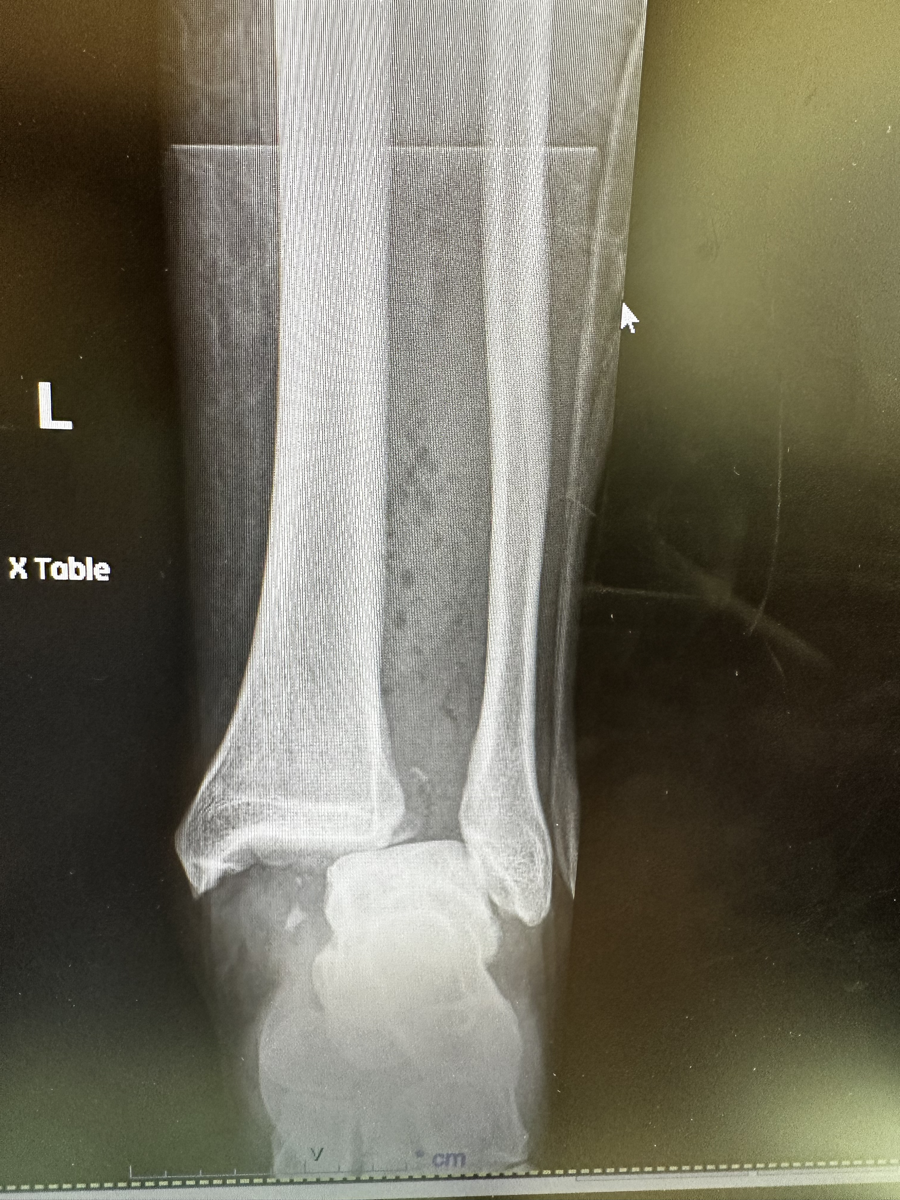

X-Ray of a fractured ankle.

Thankfully, the Fire Department picked me up in no time flat and by 8 AM I was in the emergency room.  X-rays showed that I had broken my tibia down at the ankle joint s well as my fibula up closer to my knee.  By 11 AM I was being rolled into surgery, with a slight worry that my surgeon my be a bit annoyed at being brought in on Christmas Day.  However, the surgery went well after a couple of days, I was sent home to start what would be a long recovery . . .

X-Ray of a fractured ankle with hardware installed.